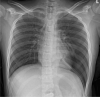

Patient concerns: A 13-year-old boy with no medical history of conditions relevant to CDH and traumatic events visited a community hospital complaining of left upper quadrant abdominal pain and vomiting over the previous 3 days. The initial chest x-ray looked like pleural effusion at a cursory glance, so a chest tube thoracotomy was performed, upon insertion food-like materials drained through the tube.

Lessons: Late presenting CDH can be misdiagnosed as pleural effusion on chest x-ray, so special attention should be given to a differential diagnosis to avoid any serious complications.